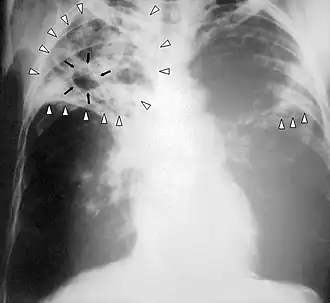

Röntgenfoto

In de tuberculosebestrijding wordt voor het aantonen van tuberculose in en bij de longen veel gebruikgemaakt van longfoto's. Longtuberculose geeft nagenoeg altijd een zichtbare fotoafwijking. Bij een slechte immuunstatus, bijvoorbeeld door hiv en aids, wordt de foto net als de mantouxtest minder betrouwbaar, omdat de afwijkingen kunnen afnemen.